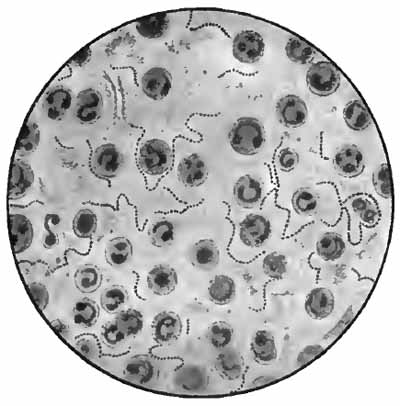

PLATE II

Heart-failure cells in sputum

FIG. 1.—Heart-failure cells in sputum, containing blood-pigment, from a case of cardiac congestion of the lungs (Jakob).

Sputum showing tubercle bacilli

FIG. 2.—A, Sputum showing tubercle bacilli stained with carbol-fuchsin and Gabbet's methylene-blue solution (obj. one-twelfth oil-immersion); B, sputum of anthracosis, showing particles of coal-dust stained with methylene-blue (obj. one-twelfth oil-immersion) (Boston).

The more important structures to be seen in unstained sputum are: elastic fibers, Curschmann's spirals, [p. 27] Charcot-Leyden crystals, fibrinous casts, the ray fungus of actinomycosis, and molds. Pigmented cells, especially the so-called "heart-failure cells" (p. 43), are also best studied without staining (Plate II, Fig. 1).

In films stained by Gabbet's method tubercle bacilli, if present, will be seen as slender red rods upon a blue background of mucus and cells (Plate II, Fig. 2). They average 3 to 4 µ in length—about one-half the diameter of a red blood-corpuscle. Beginners must be warned against mistaking the edges of cells, or particles which have retained the red stain, for bacilli. The appearance of the bacilli is almost always typical, and if there seems room for doubt, the structure in question is probably not a tubercle bacillus. They may lie singly or in groups. They are very frequently bent and often have a beaded appearance. It is possible that the larger, beaded bacilli indicate a less active tuberculous process than do the smaller, uniformly stained ones. Sometimes they are present in great numbers—thousands in a field of the one-twelfth objective. Sometimes several cover-glasses must be examined to find a single bacillus. At times they are so few that none are found in stained smears, and special methods are required to detect them. The number may bear some relation to the severity of the disease, but this relation is by no means constant. The mucoid sputum from an incipient case sometimes contains great numbers, while sputum from large tuberculous cavities at times contains very few. Failure to find them is not conclusive, though their absence is much more significant when the sputum is purulent than when it is mucoid.

(1) Pus-corpuscles are present in every sputum, and at times the sputum may consist of little else. They are the polymorphonuclear leukocytes of the blood, and appear as rounded cells with several nuclei or one very irregular nucleus (Fig. 8 and Plate II, Fig. 2). They are frequently filled with granules of coal-dust and are often much degenerated. Such coal-dust-laden leukocytes are especially abundant in anthracosis, where angular black particles, both intra- and extra-cellular, are often so numerous as to color the sputum (Plate II, Fig. 2, B). Occasionally mononuclear leukocytes are present.